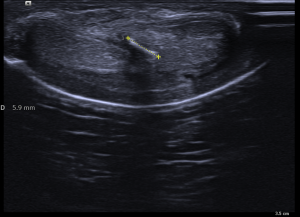

333.Revisión patología testicular. El Varicocele. Tipos y Clasificación.

Son venas del plexo pampiforme de aspecto tortuoso y dilatadas por encima de los 2 mm.

Medida superior a 2 mm. Grado 1.

Clasificación basado en el diámetro venoso del plexo pampiniforme (en reposo):

Grado 1: Entre 2,5 y 4 mm

Grado 2: Entre 4 y 5 mm

Grado 3: Mas de 5 mm

Estas medidas son de una de las clasificaciones que se usan para el estudio del varicocele. Hay alguna otra de la que hablaremos más adelante, pero esta me parece sencilla para comprender esta habitual figura patológica.

Estas medidas son en reposo y aumentan con la maniobra de valsalva. Ojo.

Existe aumento de flujo con la maniobra de Valsalva como puedes ver en el vídeo.